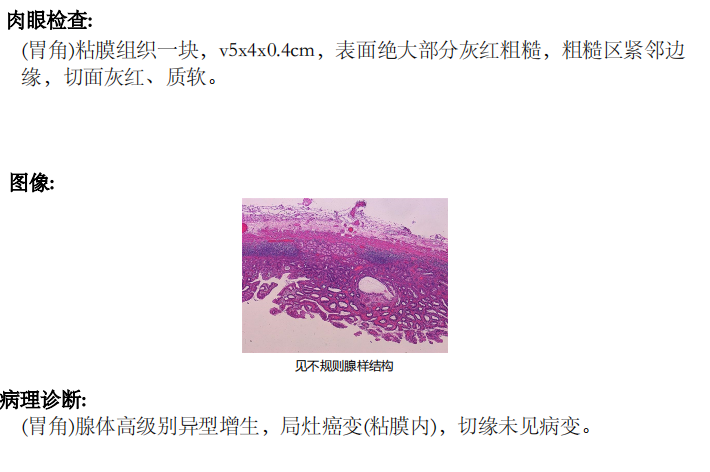

图5术后病理报告

术后病理报告 (胃角)腺体高级别异型增生,局灶癌变(黏膜内),切缘未见病变,病变已被完整切除。患者术后恢复良好,三日后顺利出院。此次手术的成功,为早期胃癌患者减少了痛苦,提高了生活质量。